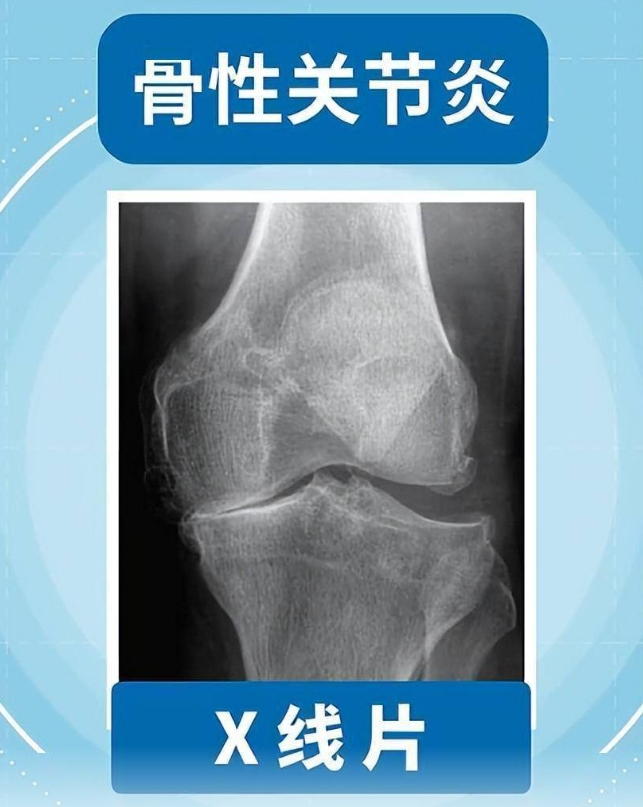

搜狐新闻客户端:且行且珍“膝”!膝盖脆弱的你,请收好这份护“膝”秘籍